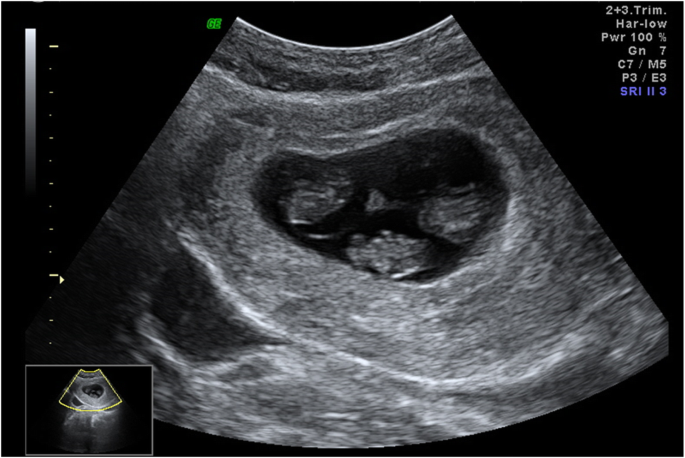

Intrauterine fetal demise , also known as stillbirth, is the death of a baby in utero . Next, Flo investigates the contributing factors and symptoms commonly associated with intrauterine fetal demise . Intrauterine fetal demise can occur at any stage of pregnancy, including labor and delivery .

Intrauterine fetal demise . IUFD . Intrauterine fetal death (IUFD) URL of Article . Fetal death in utero (FDIU), also known as intrauterine death ( IUD ), is the term used when the death of a fetus occurs after the 20th week of pregnancy . Prior to this, it is considered a miscarriage . On this page: